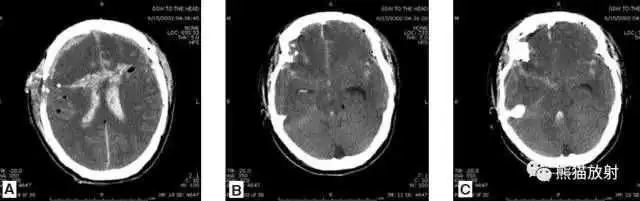

高血压性脑出血:

- 自发性出血;

- 继发于长期高血压及慢性血管病;

- 常见于基底节区、丘脑、脑桥、小脑。

A:占位效应,相邻脑沟、脑池消失;

F:脑出血破入四脑室。

▲

钩回疝:

是当代偿机制不能适应占位性病变时的结果。

基底节区大量高血压性脑出血,破入脑室及蛛网膜下腔,周围水肿,脑干周围空间消失;脑干出血、脑积水。